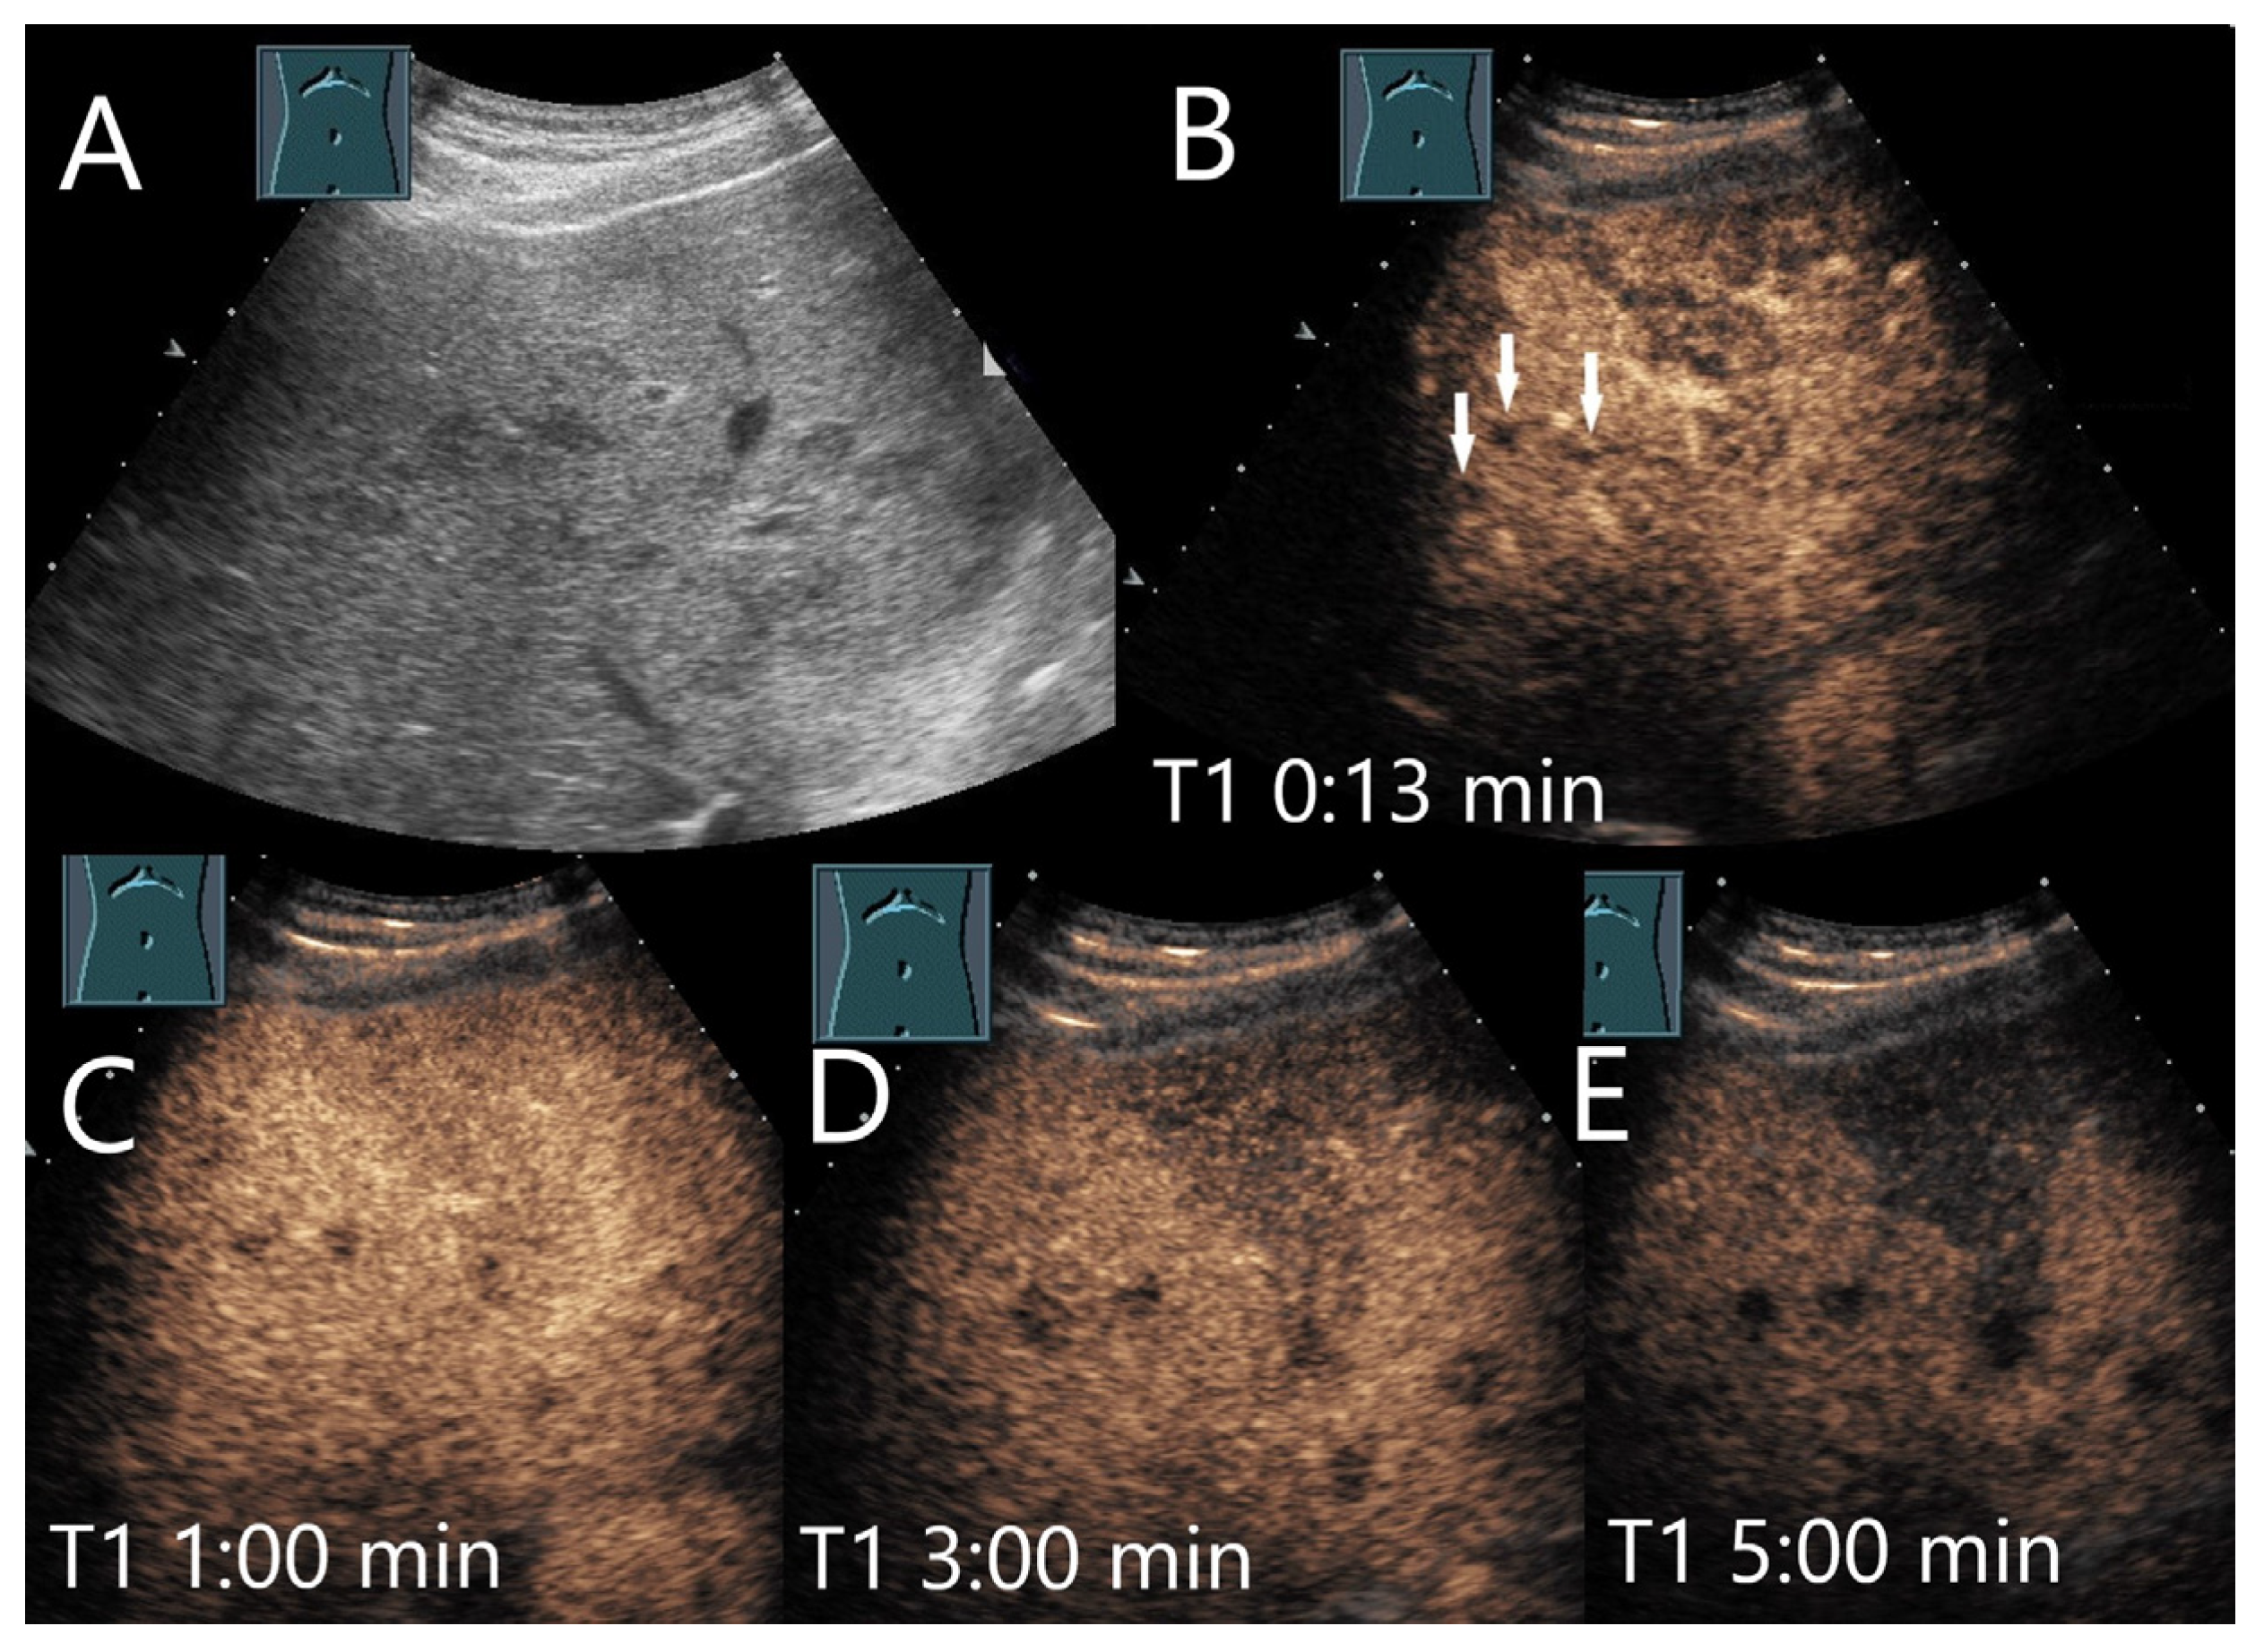

| Abscesses | Hypo-/anechoic. | Hyperenhancement in phlegmonous stage, transient hyperenhancement in surrounding parenchyma. Non-enhancement of necrotic parts. Honeycomb sign. | Early washout. | Formation of thromboses of the small hepatic and portal veins, as well as pylephlebitis of the small portalvenous vessels. |

| IPT | Mostly hypoechoic, irregular shapes. | Arterial hyperenhancement, Homogenous, heterogenous, rim like. | Early washout. | Obliterative phlebitis is due to an inflammatory infiltration of the vessel walls and lumina and thrombosis, varying degrees of fibrosis. |